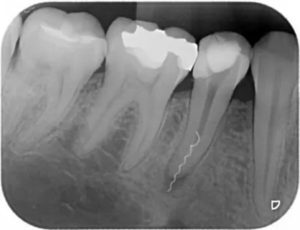

| Рис. 3 | На представленных снимках, обломанный инструмент (рис. 3) был извлечен из канала путем расширения просвета вокруг обломка. На рис. 4 тот же зуб с запломбированным каналом и как осложнение при данной манипуляции видна перфорация в области бифуркации корня. | Рис. 4 |